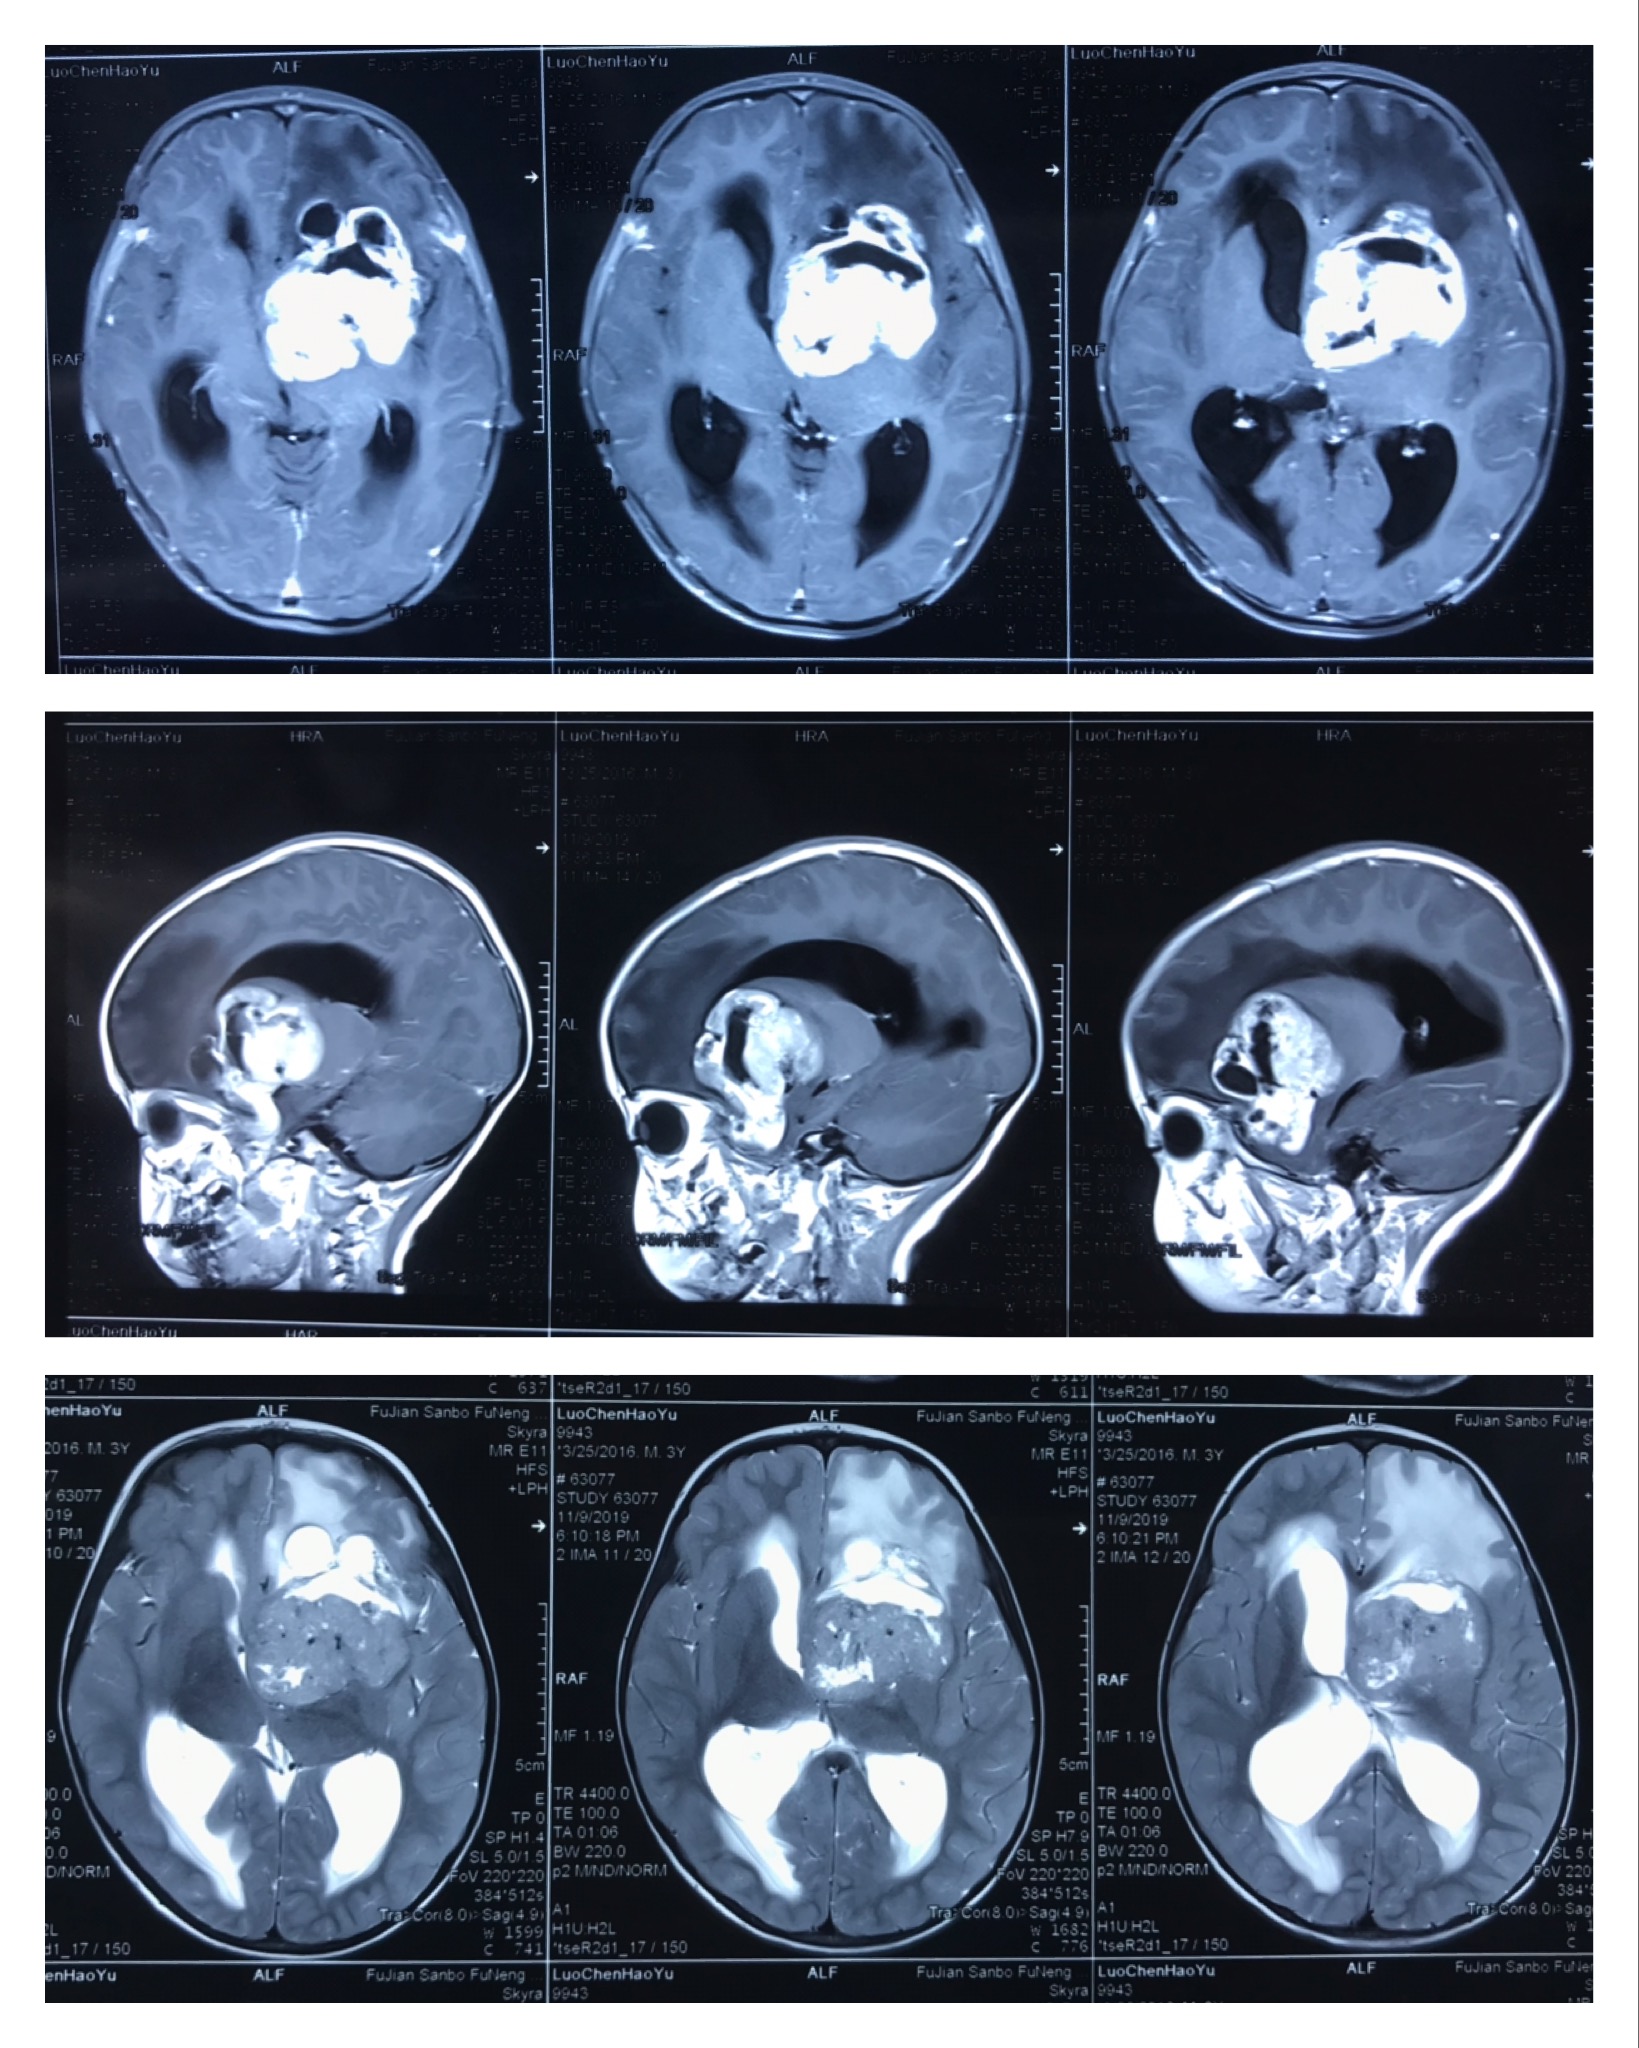

3岁男孩童童(化名)自出生以来间断性呕吐,家属以为孩子体质虚弱,到各大医院求医治疗,却不见好转。近来童童头痛频发,颈部向左侧倾斜,还出现尿失禁、流涎等症状。家属慌了,立即将孩子送至某省级三甲医院就诊。然而,检查结果犹如晴天霹雳,原来童童颅内长了巨大肿瘤,并伴有梗阻性脑积水。怎么办呢?上哪儿寻找小儿神经肿瘤方面的专家?在医生的引荐下,求医心切的家属来到福建三博福能脑科医院,向擅长脑肿瘤及小儿神经系统疾病治疗的林志雄教授问诊。经过详细检查发现,童童的病变区域位于大脑左侧基底节区,为前颅窝底肿瘤,从影像学片子上看,肿瘤巨大,已压迫重要结构,波及鞍区、前颅底、侧脑室、脚间窝。童童病情危重,需尽快手术切除肿瘤!

▲术前影像

▲术后影像